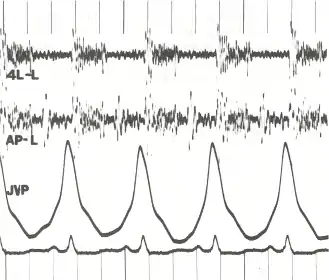

فرط ضغط الدم الرئوي الوريدي (الذي يكون في الوريد الرئوي) يَظهر عادةً مع أعراض ضيق النفس الإضّجاعي أو ضيق النَفس اللَّيلِي الانتيابي (وهو ضيق النفس عند الاضجاع أو النوم), بينما فرط ضغط الدم الرئوي الشرياني لا يُظهر هذا النوع من الأعراض. يتم اخذ تاريخ عائلي شامل لتحديد ما إذا كان المرض متوارث عائلياَ. وأخذ تاريخ التّعرّض لبعض انواع الأدوية والمواد مثل الكوكايين، الميثامفيتامين، الإيثانول (الذي يؤدي إلى التشّمع الرئوي) و التّبغ (الذي يؤدي إلى نُفاخ الرئة). يتم اجراء الفحص السريري للبحث عن علامات فرط ضغط الدم الرئوي، من هذه العلامات انفصال صوت القلب الثاني (S2) وارتفاع صوت انغلاق الصمام الرئوي بالإضافة إلى صوت رفيع (كصوت التنهيدة ) يتم سماعه بجانب عظمة القص والذي يشير إلى تضّخّم في عضلة الأُذين الأيمن في القلب. قد يحدث احتقان عام في اجهزة الجسم المختلفة نتيجة فشل الجانب القلبي الأيمن، ومن علاماته تمدد الوريد الوداجي، الوذمة القدميّة (تجمع السوائل في القدم), الاستسقاء، المنعكس الكبدي الوداجي، التعجّر وغيرها. يتم البحث ايضاً عن دلائل قصور الصمام ثلاثي الشرفات ودلائل قلس الصمام الرئوي (ارتجاع الصمام الرئوي) حيث يعتبر وجودها دليل على وجود فرط ضغط الدم الرئوي.

يتم القيام بالفحص السريري للبحث عن الاعراض الاعتيادية لفرط ضغط الدم، وهي تشمل تغيّر في اصوات القلب، مثل انفصال واسع في الصوت الثاني للقلب، ارتفاع صوت انغلاق الصمام الرئوي (هو جزء من صوت القلب الثاني), صوت كالنهدة يتم سماعه بجوار عظمة القص، وجود وسماع الصوت الثالث للقلب (الذي يكون عادةً غير مسموع) وارتجاع رئوي. هناك علامات اخرى تشمل ارتفاع الضغط في الوريد الوداجي، وذمة طرفيّة (استسقاء في الاطراف كالكاحل والقدم), استسقاء في البطن نتيجة تجمع السوائل، انعكاس كبدي وداجي وتعجّر الأصابع والأظافر (تخن النهايات).